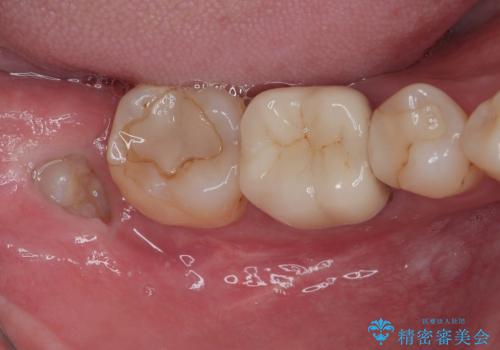

右下の親知らずを抜きたい 親知らず抜歯

担当医 有澤哲郎